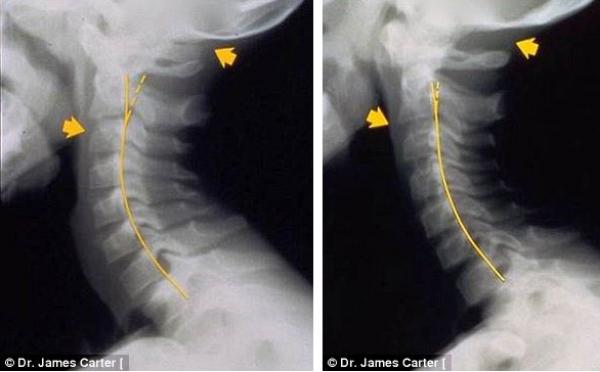

وأرفق الطبيب تحذيراته بمجموعة من صور الأشعة السينية لبعض الحالات المصابة بمرض التنكسية في العمود الفقري نتيجة استعمال الهاتف الذكي لفترة طويلة، توضح تشوهات وآلام في الرأس والرقبة والكتف والظهر.